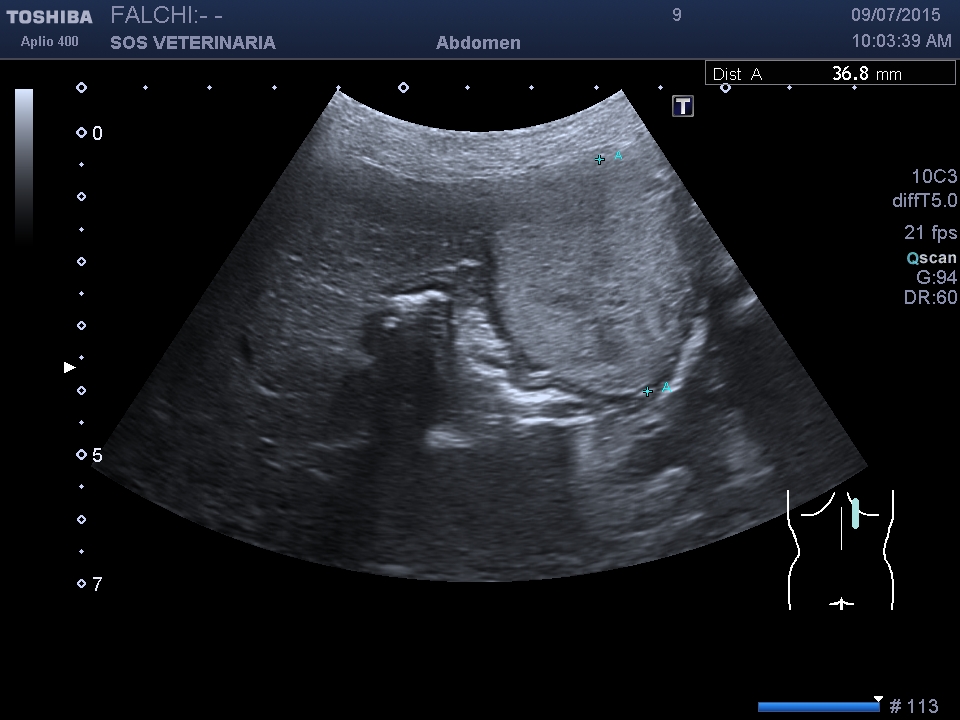

primo esame ecografico .volume surrenalico nei limiti,morfologia surrenalica rispettata , ,lesione focale epatica compatta omogenea nei settori di sx altre piu’ piccole lesioni focali meno demarcate e definite sempre nei settori di sx

ecografia di secondo livello con CEUS

fase arteriosa isoenanchement

fase portale e tardiva ipoenachemente